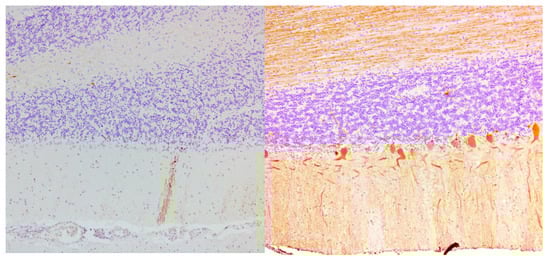

| Mittelbronn 2010, Germany | 1 | Brain | Loss of Purkinje cells & cerebellar granular layer cells; Cerebellar atrophy and astrocytic gliosis; Severe neuronal loss inferior olives & accumulation of corpora amylacea. Cerebral reactive astrogliosis and microglial activation Inflammation dominated by CD8+/granzyme B+ & CD20-/CD138- diffuse infiltrates & perivascular cuffing in the cerebellum and brainstem |

| Nanri 2011, Japan | 1 | Brain | Loss of Purkinje cells; Minimal cerebellar atrophy; Mild Bergmann gliosis. Empty basket cells, Edematous splitting of Purkinje cell layer, loss of granular cells. No lymphocytic infiltration (CD3-, CD4-, CD8-, CD20-, CD68-, CD79A-) |